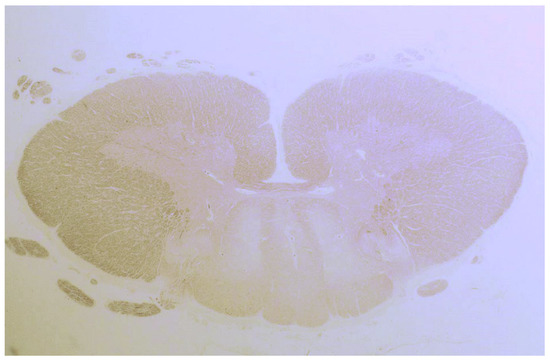

| Bhatia 1995, UK | 1 | Brain Spinal cord | Loss of Purkinje cells and cells in inferior olives; Cerebellar gliosis; Astrocytosis of the granular layer, dentate nucleus & inferior olives |

| Cooke 1966, UK (I) * | 9 | Brain Spinal cord | Loss of Purkinje cells; atrophy and gliosis of the dentate nucleus, cerebrum, inferior olives, thalamus and hypothalamus; demyelination of post. & ant.-lat. columns; focal perivascular lymphocytic cuffing, chromatolysis and sudanophil lipophages throughout the CNS. |

| Finelli 1980, USA | 1 | Brain Spinal cord | Loss of Purkinje and granular layer cells; Neuronal loss & gliosis basal ganglia, inferior olives, substantia nigra; Demyelination ant. & lat. corticospinal tracts |

| Hadjivassiliou 1998, UK | 2 | Brain Spinal cord | Loss of Purkinje cells; Cerebellar atrophy & astrocytic gliosis & vacuolation of neutrophils; Diffuse infiltration of lymphocytes & perivascular cuffing of T-lymphocytes in the cerebellum and the post. columns |

| Kinney 1982, USA | 1 | Brain | Loss of Purkinje cells; atrophy, gliosis of the dentate nucleus, cerebellar granular layer, thalamus, hypothalamus & periaqueductal grey; Senile plaques in the neocortex & hippocampi; Cerebral gliosis subcortical & white matter |

| Mittelbronn 2010, Germany | 1 | Brain | Loss of Purkinje cells & cerebellar granular layer cells; Cerebellar atrophy and astrocytic gliosis; Severe neuronal loss inferior olives & accumulation of corpora amylacea. Cerebral reactive astrogliosis and microglial activation Inflammation dominated by CD8+/granzyme B+ & CD20-/CD138- diffuse infiltrates & perivascular cuffing in the cerebellum and brainstem |

| Nanri 2011, Japan | 1 | Brain | Loss of Purkinje cells; Minimal cerebellar atrophy; Mild Bergmann gliosis. Empty basket cells, Edematous splitting of Purkinje cell layer, loss of granular cells. No lymphocytic infiltration (CD3-, CD4-, CD8-, CD20-, CD68-, CD79A-) |